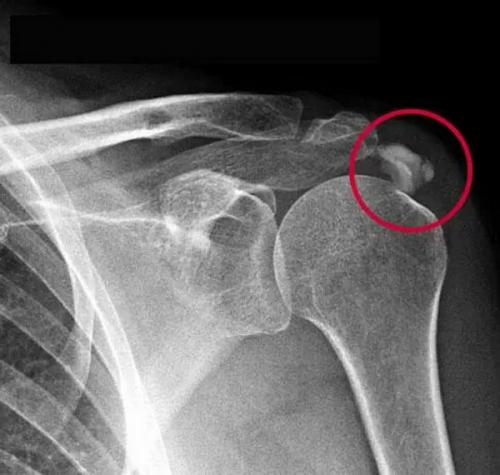

Отложение солей на плечах. Кальцифицирующий тендинит ротаторной манжеты плеча (Кальцифицирующий тендинит плеча)

Кальцифицирующий тендинит плеча (плечевого сустава) – это заболевание при котором происходит отложение солей кальция (гидроксиапатита кальция) в сухожилиях и мышцах вращательной манжеты плеча. При этом возникает реактивное воспаление тканей вокруг кальциевых отложений, что сопровождаться интенсивной болью, местным повышением температуры, отечностью задействованных в патологическом процессе тканей и ограничением объема движений в плечевом суставе.

Впервые появление кальцитатов в области плечевого сустава описал C. F. Painter в далеком 1907 году. Более подробно патологию, с точной локализацией проявления в толще сухожилий ротаторной манжеты плечевого сустава, описал E. A. Codman в 1934 году.

Кальцифицирующий тендинит плеча довольно распространенное заболевание

Наиболее часто оно возникает у лиц старше 40 лет. По статистике чаще патология встречается у женщин возрастом 30-50 лет. По локализации возникновения чаще всего отложения солей кальция обнаруживают в сухожилии надостной мышцы (приблизительно 80% случаев) остальные случаи – подлопаточная, подостная мышца или одновременная локализация в нескольких мышцах и сухожилиях.

Отложения солей кальция иногда достигают существенных размеров и становятся серьезной проблемой в жизни человека.